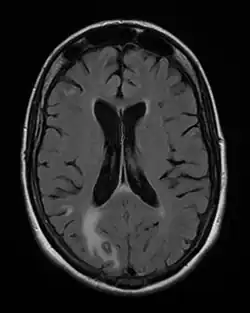

Toxoplasmosis in humans is diagnosed through biological, serological, histological, or molecular methods, or by some combination of the above.[62] Toxoplasmosis can be difficult to distinguish from several other conditions, especially ones that are common in HIV/AIDS and immunocompromised patients, and can cause central nervous system problems and brain lesions.[68] Toxoplasmosis is most commonly mistaken for primary central nervous system lymphoma, both conditions cause lesions in the brain, but in about 50-80% of cases the lesions appearances can be very similar on imaging, and exist in an area of the brain that makes biopsying too risky, however the main difference is lymphoma typically causes a single lesion in the subependymal region, and toxoplasmosis causes multiple lesions scattered through the basal ganglia.[69] Other conditions that can present as toxoplasmosis on a differential diagnosis are metastatic brain lesions, progressive multifocal leukoencephalopathy[70], CNS tuberculosis[71], bacterial or fungal brain abscess, cytomegalovirus (CMV),[72] and herpes simplex encephalitis.[68][73]

Due to the absence of obvious symptoms,[13][14] hosts easily become infected with T. gondii and develop toxoplasmosis without knowing it. Although mild, flu-like symptoms occasionally occur during the first few weeks following exposure, infection with T. gondii produces no readily observable symptoms in healthy human adults.[7][20] When the infection enters a latent phase, during which only bradyzoites (in tissue cysts) are present;[21] these tissue cysts and even lesions can occur in the retinas, alveolar lining of the lungs (where an acute infection may mimic a Pneumocystis jirovecii infection), heart, skeletal muscle, and the central nervous system (CNS), including the brain.[22] Cysts form in the CNS (brain tissue) upon infection with T. gondii and persist for the lifetime of the host.[23] Most infants who are infected while in the womb have no symptoms at birth, but may develop symptoms later in life.[24]